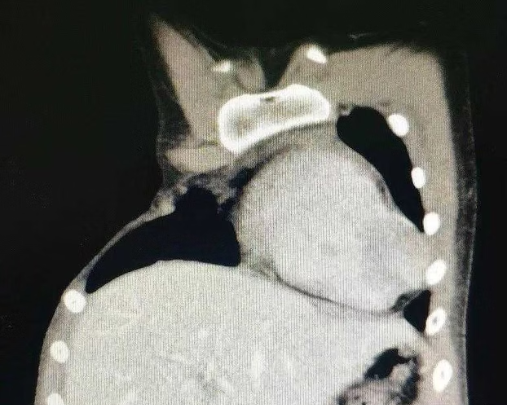

A rare congenital condition that affects the development of the chest wall and sometimes the upper limbs. Poland syndrome is mainly characterized by abnormalities of the chest wall bony structures (including ribs and costal cartilages) and soft tissues (including the pectoralis major, pectoralis minor, and breast tissue), which result in clinical manifestations such as chest wall depression, chest wall defects, and breast hypoplasia in affected individuals. In addition, some patients also present with ipsilateral upper limb anomalies on the affected side of the chest wall, manifested as syndactyly or ectrodactyly. Understanding the prevalence of this condition and its potential causes is important for early recognition and appropriate care.

The incidence of Poland syndrome is estimated at approximately 1 in 20,000 to 70,000 live births. It is more common in males and usually affects the right side. Bilateral involvement is extremely rare. Due to its low incidence, many people may not realize they have the condition until noticeable chest wall abnormalities and symptoms such as chest tightness and shortness of breath appear.

The exact Poland syndrome cause is unknown. Researchers believe that disruption of blood supply to the chest wall during early fetal development may lead to underdeveloped muscles, ribs, and breast tissue. Genetic factors may also play a role, as Poland syndrome can recur in the same family and gene mutations have been identified on the chromosomes of affected individuals. Other explanations have been proposed clinically, such as smoking and autosomal dominant inheritance.